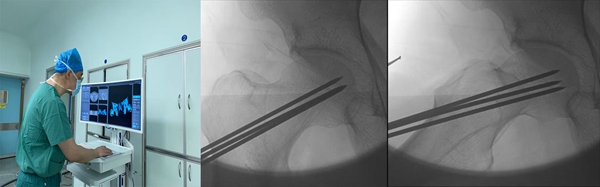

患者出现双侧股骨头缺血性坏死,王坤正教授查看病人情况及影像学检查后,建议患者采用机器人辅助下髓芯减压术保髋治疗。在骨关节外科杨佩主任医师、宋金辉副主任医师、王春生副主任医师的指导下,由田润副研究员完成了双侧机器人辅助下髓芯减压术。手术通过比对术前ct数据与术中x片完成体表定位,所有减压克氏针均一次性准确到达坏死区,手术过程无切口,无出血,仅使用C型臂透视2次,双侧减压操作仅用时26分钟,术后患者髋关节疼痛缓解。